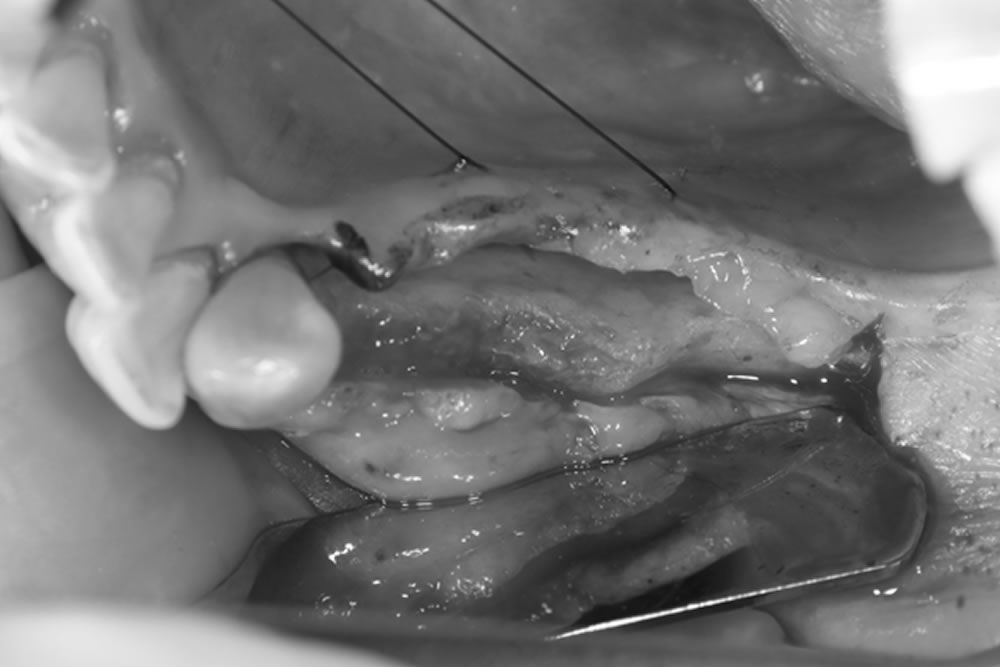

FGG(遊離歯肉移植術)の実施

移植した歯肉が安定して固定・生着できるよう、受容床を適切に形成します。

上顎の口蓋(上顎の内側)から、歯肉の移植片を慎重に採取します。

移植片が適切な位置で生着できるよう、受容床に密着させた状態で縫合し、しっかりと固定します。

FGG(遊離歯肉移植術)の経過

移植した歯肉は良好に生着しており、上顎口蓋の採取部位についても順調に治癒が進んでいます。

術前は歯肉が非常に薄く大半が可動粘膜でしたが、術後はインプラント周囲に角化粘膜が獲得できました。